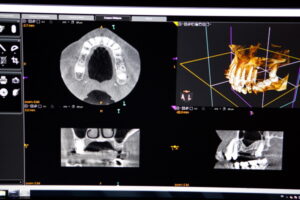

通常のレントゲンが平面的な画像しか得られないのに対し、三次元画像診断装置である歯科用CTでは立体的な画像を構築することができます。

複数の方向から連続的に撮影を行い、得られた多数の画像データをコンピューターで処理することにより、あらゆる角度からの断面画像や三次元画像を作成可能です。

これにより、歯や顎骨の形態、神経や血管の走行、病変の広がりなどをより詳細に把握できるというメリットがあります。

医科用CTと比較して、歯科用CTは撮影範囲が口腔周囲に限定されているため、被ばく量が少なく、撮影時間も短いという特徴があります。

また、座位や立位で撮影できる機種が多いため、患者さんへの負担も軽減されています。